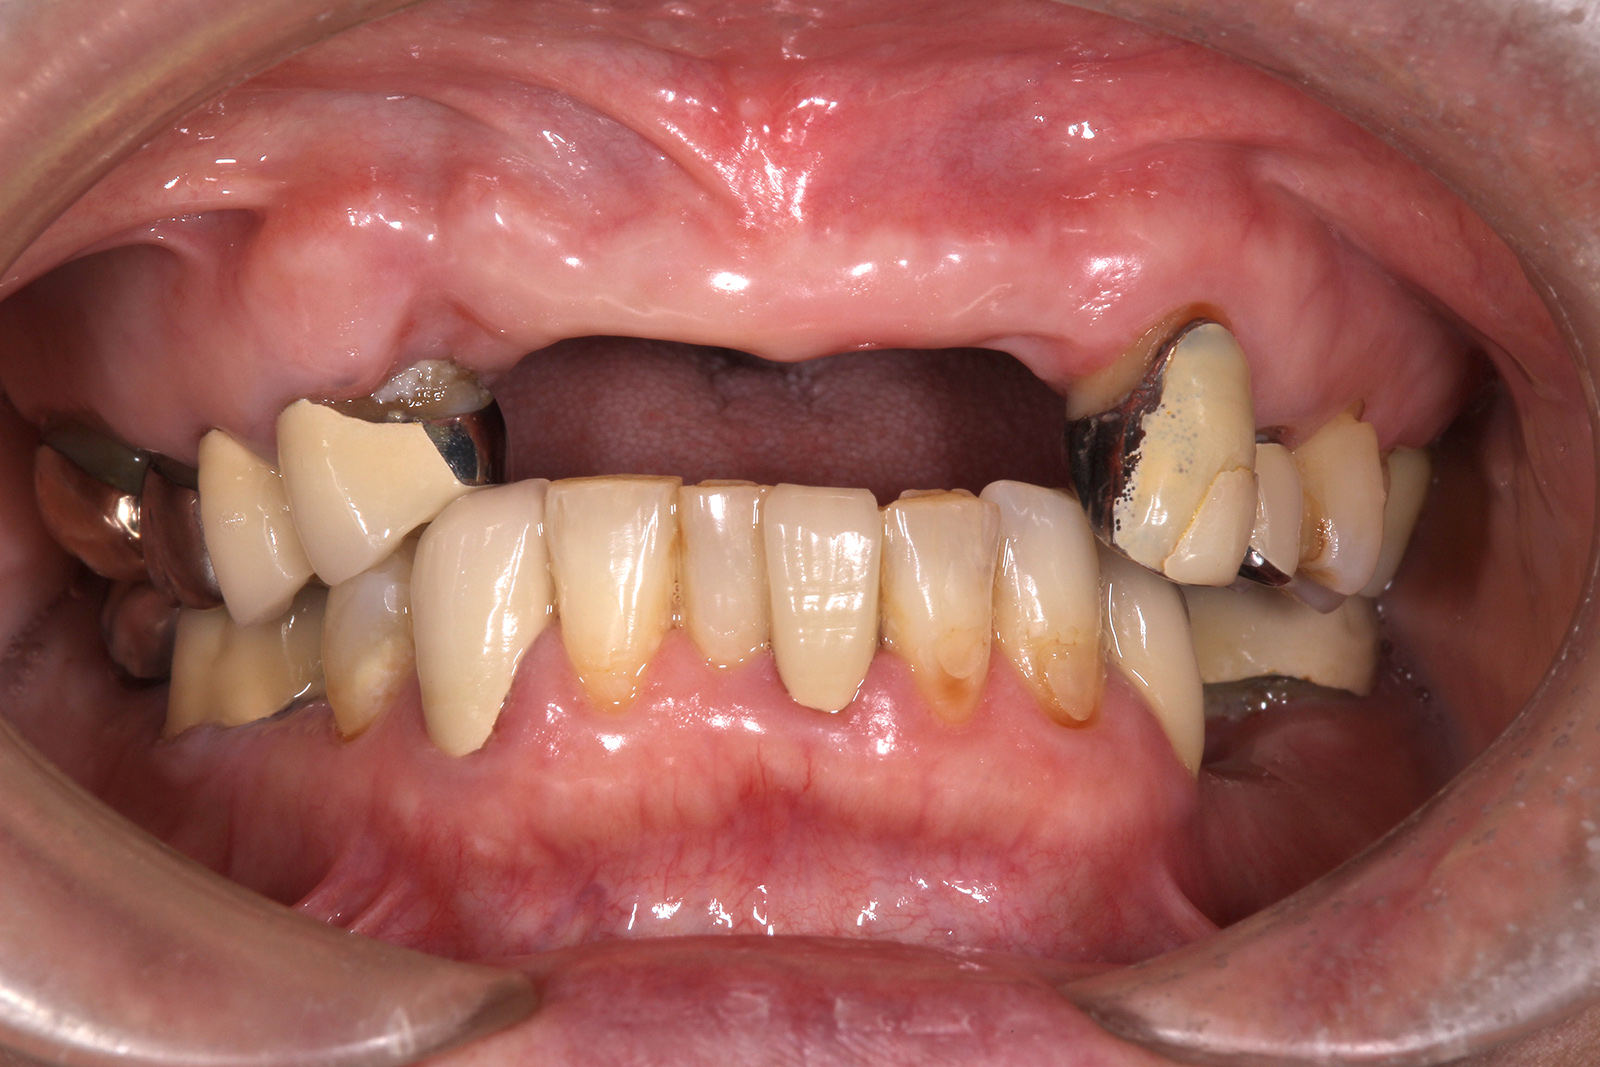

• 治療前

• 治療後

失われた上あご前歯を中心に治療。

ブロック骨移植による骨造成、結合組織移植、インプラント埋入3本、奥歯の部分矯正、セラミックによる被せ物など。

治療期間は1年6ヶ月。費用はおよそ200万円程度。

定期的なメンテナンスを行わないと、インプラント周囲炎のリスクがある。

失われた上あご前歯を中心に治療。ブロック骨移植による骨造成、結合組織移植、インプラント埋入3本、奥歯の部分矯正、セラミックによる被せ物などで、治療期間は1年6ヶ月。費用はおよそ200万円程度。定期的なメンテナンスを行わないと、インプラント周囲炎のリスクがある。